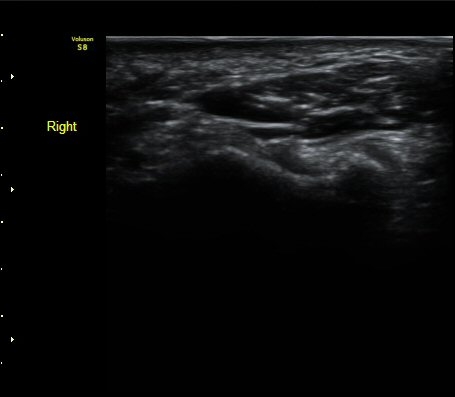

¼ÒÁö±¸ ³»Ãø¿¡ ȾÀ¸·Î ŽÃËÀÚ¸¦ ´ë¾î °¥°í¸®»À °¥°í¸® ³»Ãø¸é ÇÇÁú°ñÀ» °üÂûÇÏ´Ï(¾Æ·¡ ±×¸²)

°¥°í¸® ÇÇÁú°ñ ¿¬¼Ó¼º ¼Ò½Ç(loss of cortical continuity of hook of hamate)ÀÌ °üÂûµÈ´Ù(±×¸² 1, 2).

ÇÇÁú°ñ ¿¬¼Ó¼º ¼Ò½ÇÀº °ÇÃø°ú ºñ±³ÇØ¸é ´õ¿í ¶Ñ·ÈÇÏ´Ù(±×¸² 3, 4).